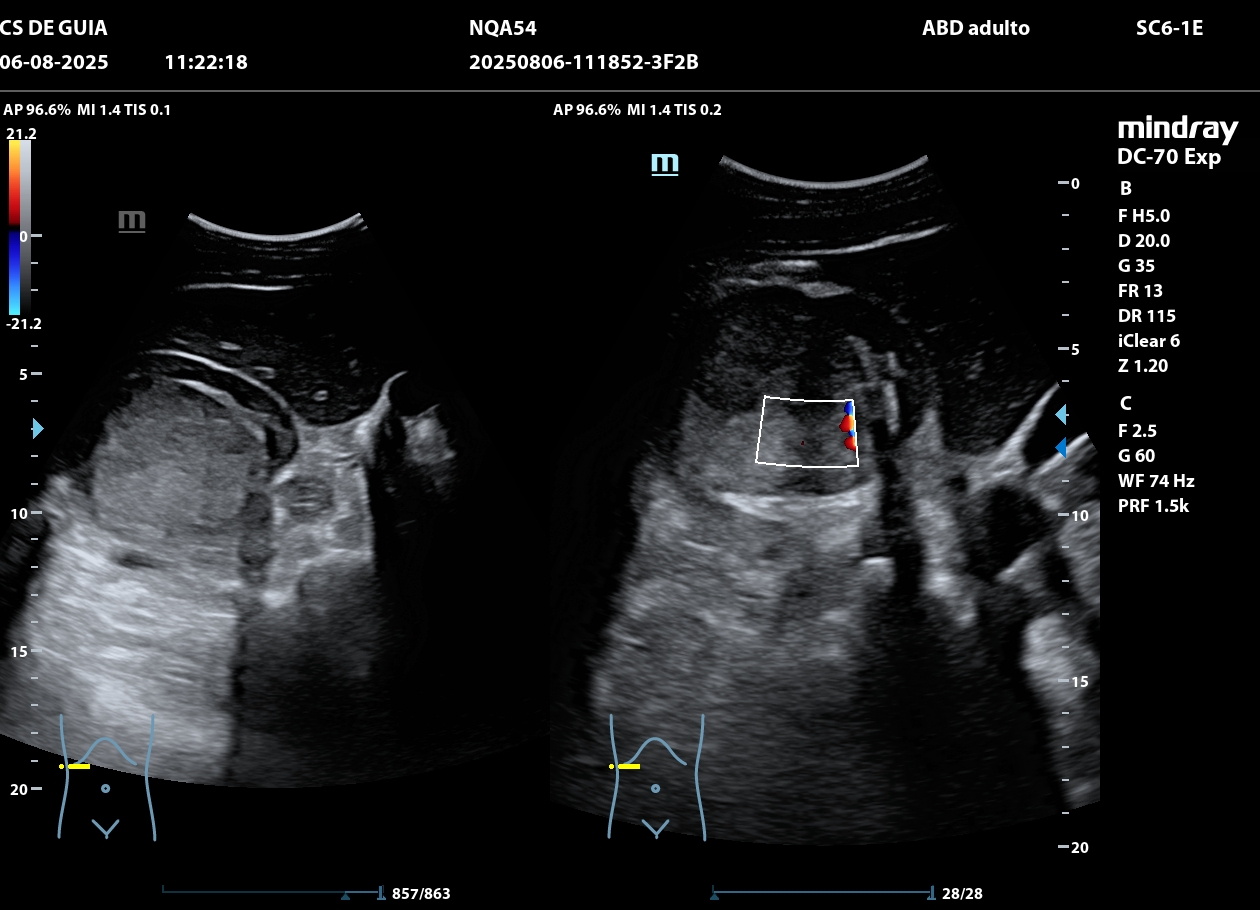

Hallazgos ecográficos

Ecografía: riñón derecho una masa isoecogénica de 7,1 x 6,3 cm de diámetro en médula renal que no deforma la cortical, vascularización periférica y sin sombra posterior.